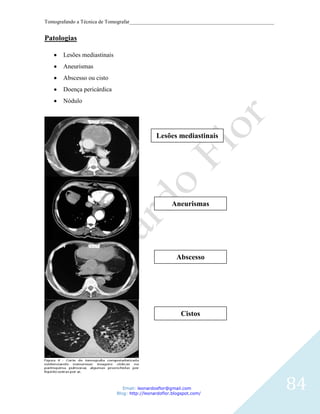

Patologias

Traumas (edema cerebral, hemorragia, hematoma extra ou subdural, hemorragia

subaracnóidea)

AVC (isquêmico ou hemorrágico).

Tumor cerebral.